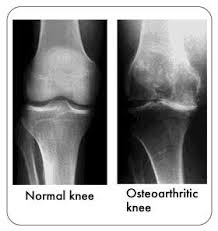

Find x ray of knee stock images in hd and millions of other royalty free stock photos illustrations and vectors in the shutterstock collection. Add to likebox 127713977 wheelchair icon simple style. X ray image of right knee ap and lateral view showing total knee arthroplasty and fractures of the tibial plateau with. This x ray shows a healthy joint with nice sharp well defined edges at the joint margins.